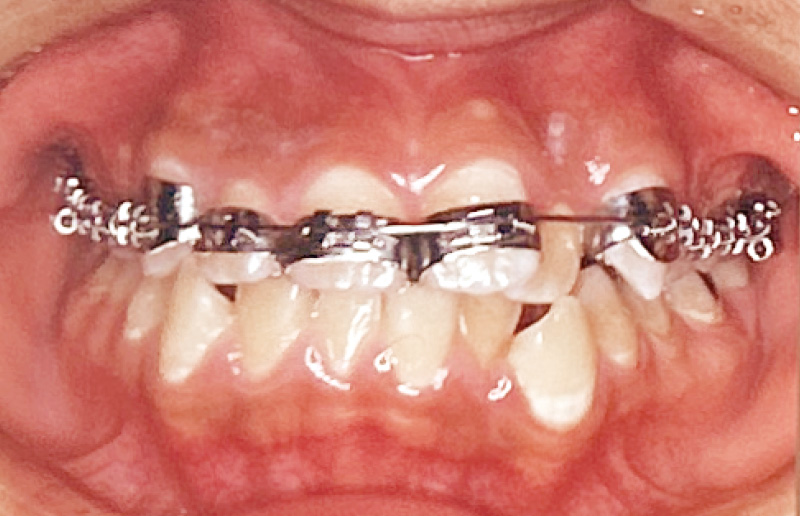

図14A, B デボンド直後のレジン残留状況比較

(上顎:「ティースプライマー」+「ボンドフィルSBⅡ」で接着。下顎:CR系光重合型矯正用接着材で接着)

A:ブラケット除去直後の口腔内写真。上顎前歯は「ティースプライマー」使用

B:下顎は光重合系レジンセメントを使用しており、ブルーライト下で発光している状態。ほとんどのレジンが歯面に残存していることがわかる。 -